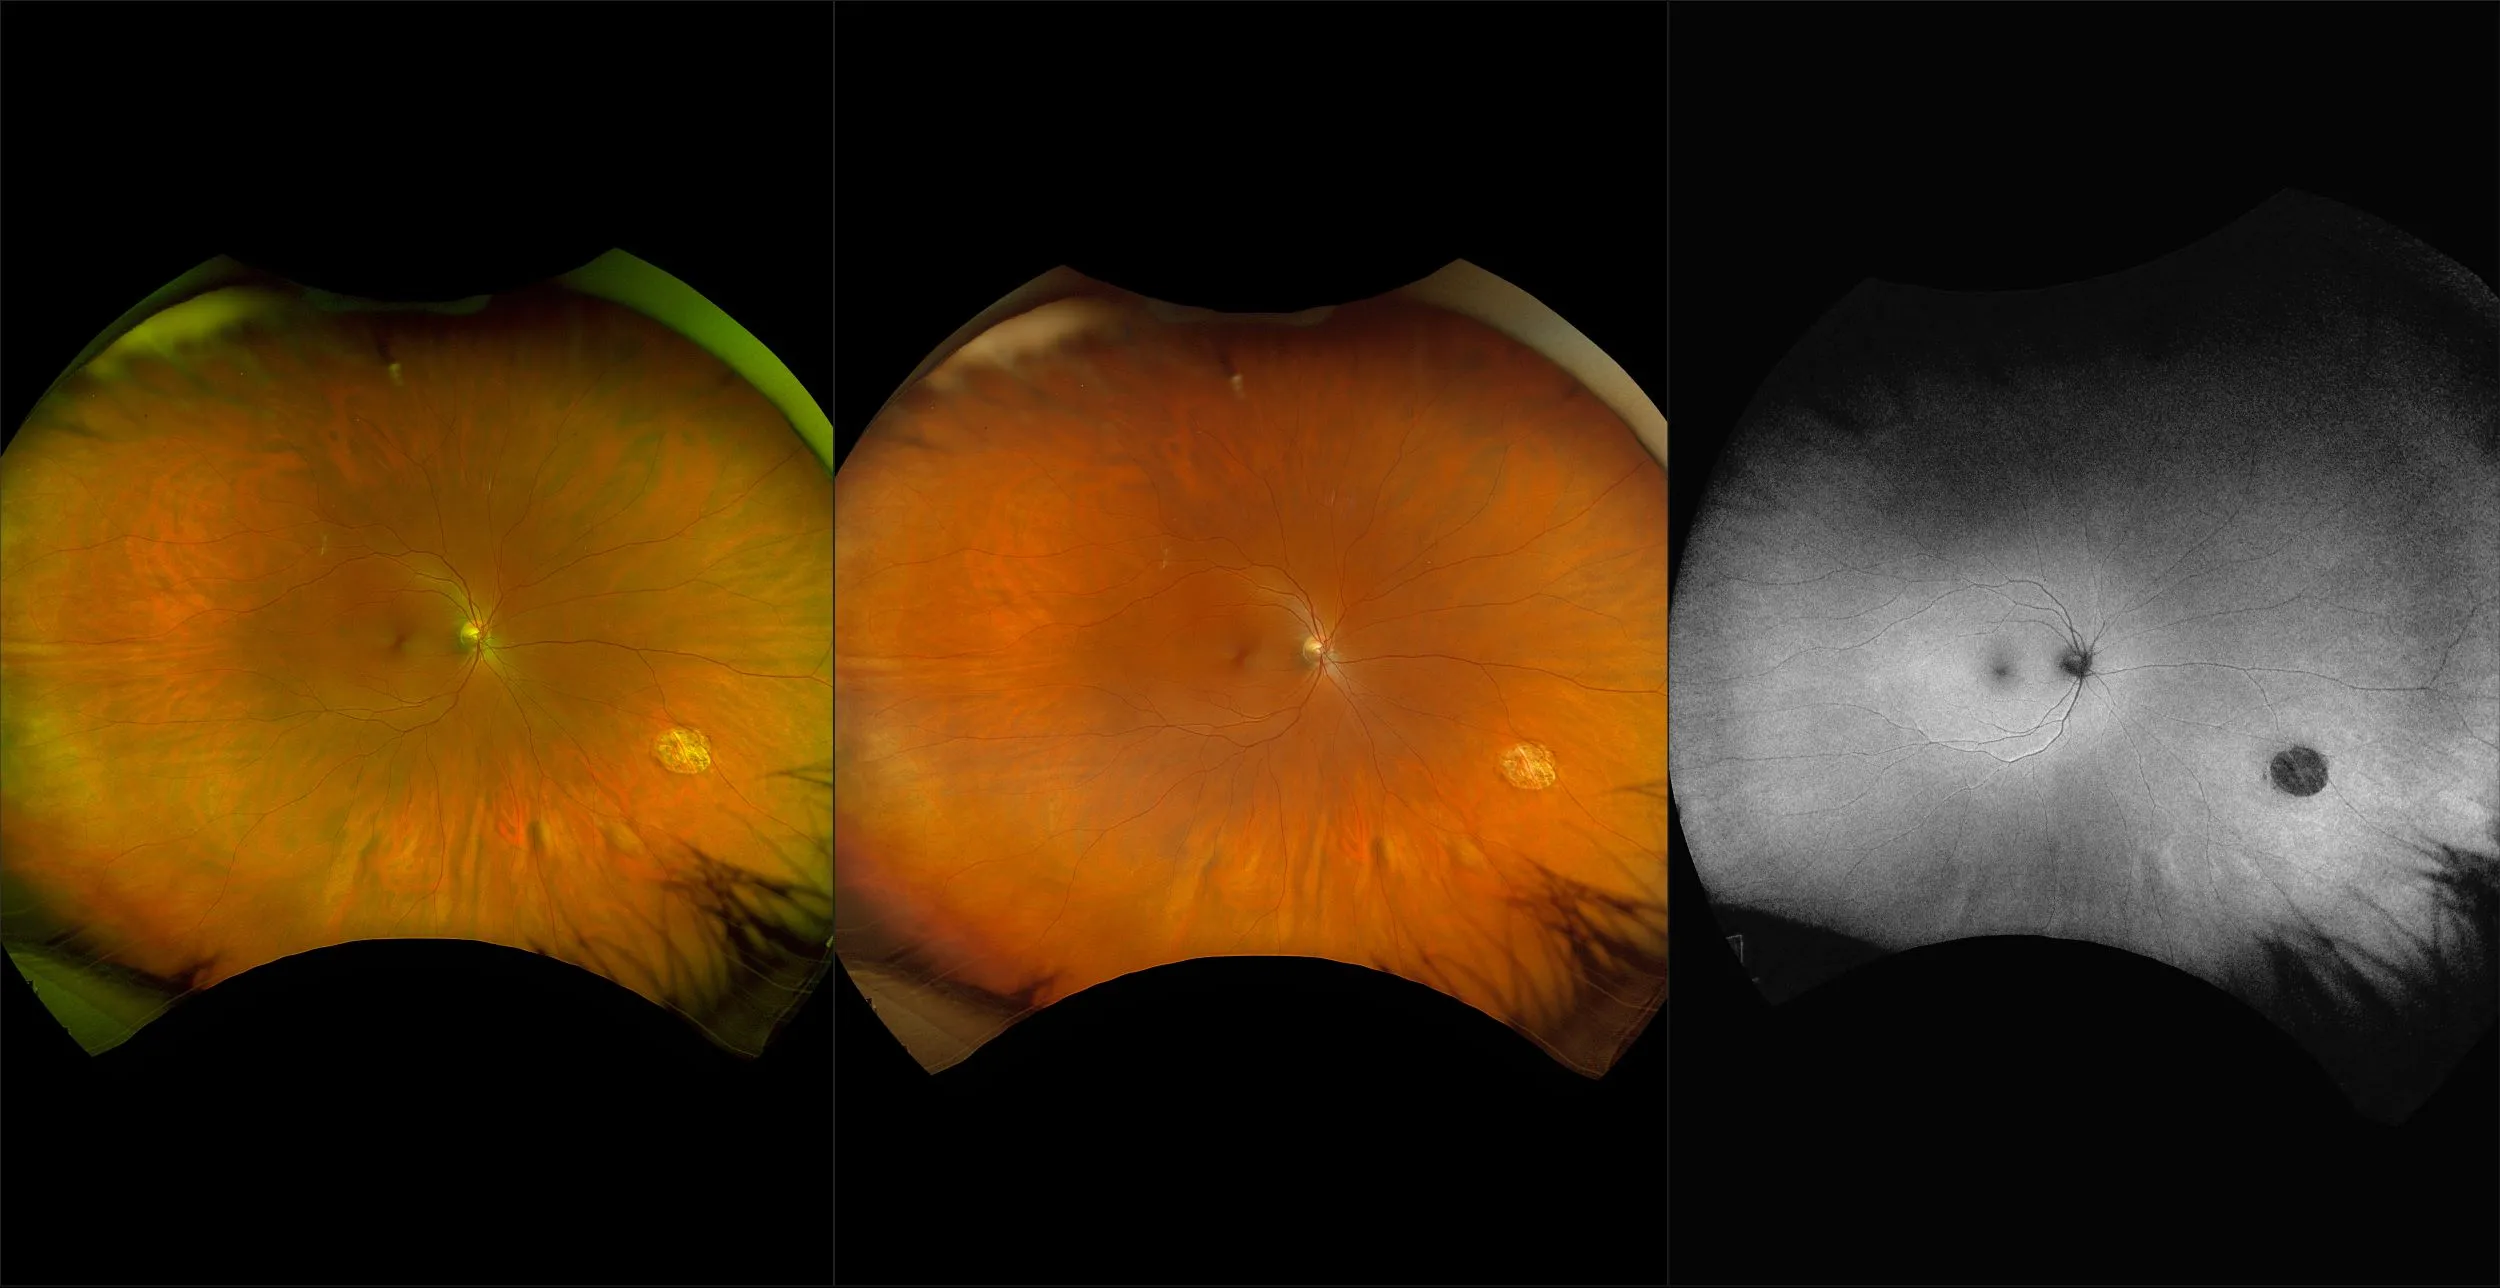

optomap® Recognizing Pathology

This material is designed as a searchable reference resource to support clinical decision-making. The information contained here should be used as general guidance when viewing optomap and OCT images from Optos devices. The differential diagnosis should be made under the direction of the responsible physician. These images were taken on the latest ultra-widefield optomap devices.

The Cases and Images

optomap Recognizing Pathology is searchable by pathology and/or optomap image modality. You may search by multiples of each selection. Each individual case is represented by the accompanying thumbnail image. Most cases include several different optomap image modalities. To view a full description of the case, please click on the thumbnail. Each image in the case will be made available through our OptosAdvance software which provides multi-dimensional visualization of digital images to aid in the analysis of anatomy and pathology. Support and pathology definitions can be found by selecting one of the buttons, above. Should you have questions, please complete the form below.